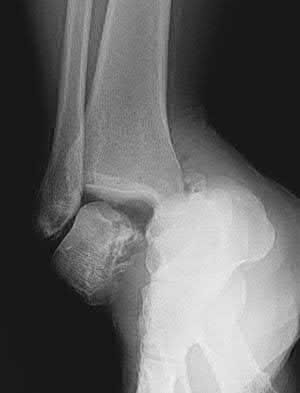

2. # A 35-year-old woman is involved in a head-on collision while driving. Initial radiographs are shown in Figures 8a and 8b. Injury to what vessel increases the risk for osteonecrosis of the injured bone?

1. Dorsalis pedis artery

2. Perforating peroneal artery

3. Lateral tarsal artery

4. Artery of the tarsal canal

5. Artery of the tarsal sinus Corrent answer: 4

The patient has a Hawkins type III talar neck fracture-dislocation with a risk of osteonecrosis ranging from 69% to 100%. Anatomic studies have shown that the artery of the tarsal canal supplies the lateral two thirds of the talar body.

The other vessels listed provide no significant contribution to the talus.